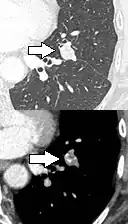

.png)

- Bubble-like lucencies in the nodule indicate cancer:[9]